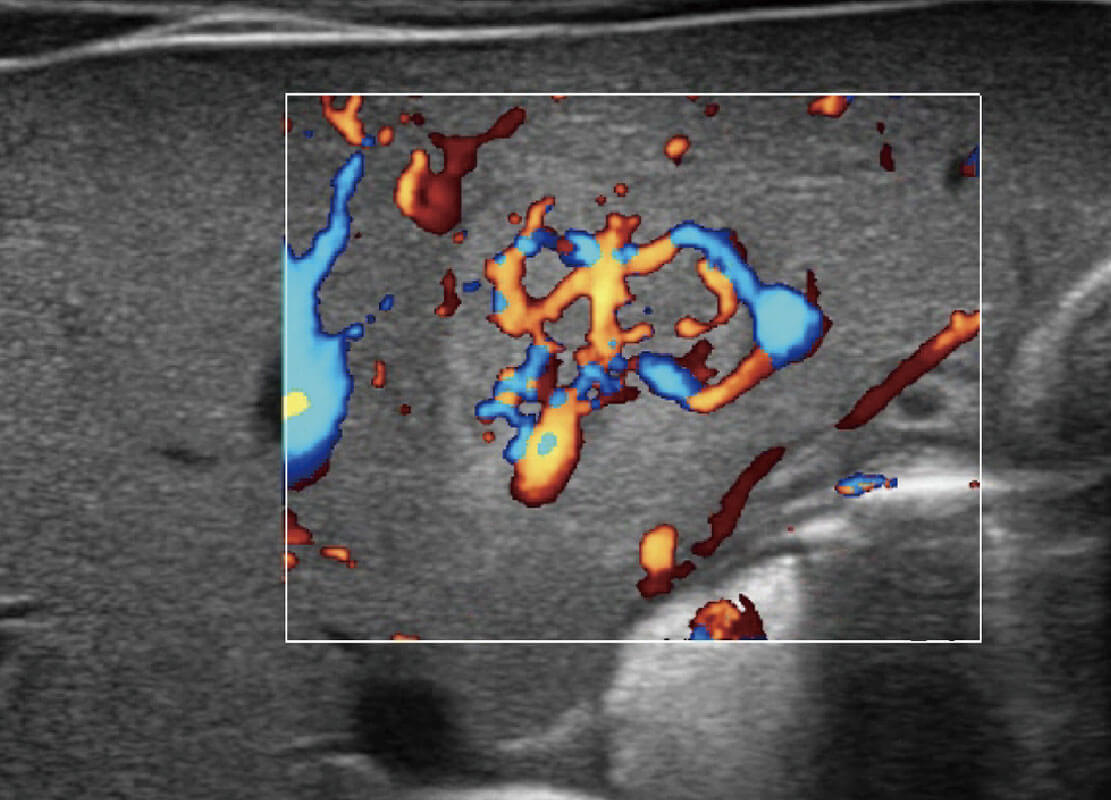

P60优异的图像质量搭载专科探头,在妇科基础疾病的诊断、卵泡生长的监测、输卵管通畅情况的判别等方面为您提供生殖应用方案。

P60搭载宽频带线阵探头、宽景成像、弹性成像技术,为您提供乳腺应用方案。P60支持高频相控阵探头、线阵探头、腹部高频探头、腹部微凸探头等,丰富的探头群搭载敏感的彩色血流成像,适用于新生儿多种脏器检测要求,满足新生儿筛查需求。

乳腺导管癌

乳腺癌显微血流

新生儿肝血管癌